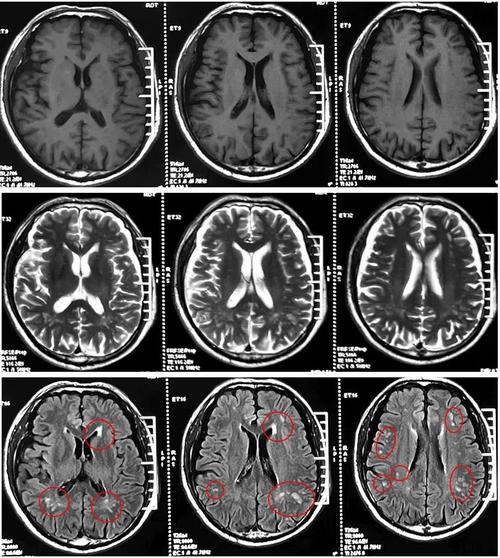

脑系核磁:

(图片来源网络,侵删)这指的是检查的部位和方法,即“头颅核磁共振成像”(MRI),这是一种非常先进的影像学检查,对脑部组织的分辨率很高,能发现CT检查看不出来的细微病变。

腔梗:

(图片来源网络,侵删)- 这是核心诊断。“腔隙性脑梗塞”的简称。

- 形成原因:我们的大脑里有非常细小的血管,叫做“穿通动脉”,这些血管为大脑深部的一些重要结构(如基底节、丘脑、脑干等)供血,当这些小血管因为各种原因(比如堵塞、变性)发生堵塞时,它所供应的那一小块脑组织就会因为缺血而坏死,形成一个微小的“洞”或“腔隙”,这个坏死区域就叫做“腔隙性脑梗塞”。

- 是“冰山一角”:脑内能被MRI看到的“少许腔梗”,说明您大脑的血管系统已经存在问题了,那些更细小、还没形成梗塞的血管,可能也已经处于不健康的状态,它预示着未来发生更大面积脑梗或其它心脑血管疾病(如心肌梗死)的风险比正常人要高。